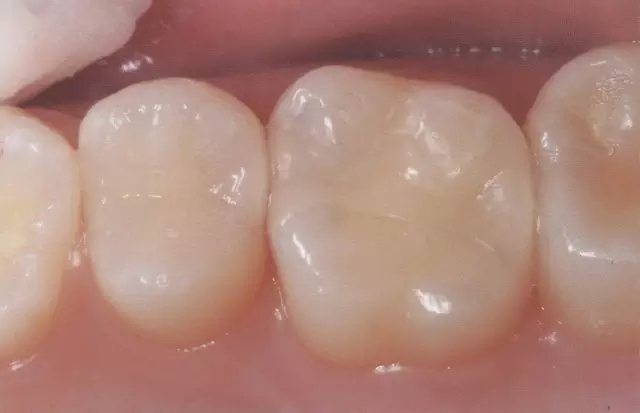

圖2 右5進(jìn)行了全瓷嵌體修復(fù),為了使受力均勻,線角需要呈圓弧狀。

圖3 全瓷嵌體的修復(fù)(右56)。鄰接面產(chǎn)生齲齒的情況(上段,中段左),去除齲齒,并佩戴嵌體(下端)。